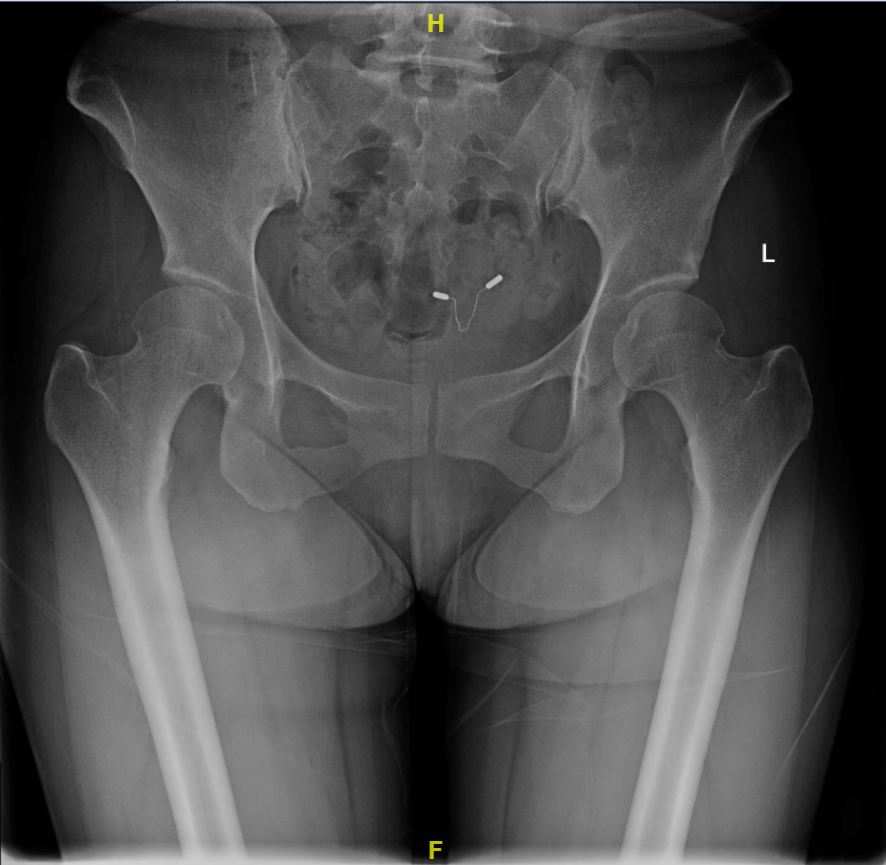

女性,38岁,因双髋关节疼痛数年,加重3个月就诊,诊断双侧髋关节发育不良,经术前详细阅片与查体,适合保髋手术,于2018-11在全麻下行右侧髋臼PAO截骨手术,术后恢复良好;随后,于2019-09全麻下行左侧髋臼PAO截骨手术,术后恢复良好;于2021-01复查发现双侧髋臼PAO截骨处骨质愈合良好,在局麻下取出内固定螺钉。

2018-11 术前:双髋关节正位X线片

2020-01 术前:双髋关节正位X线片